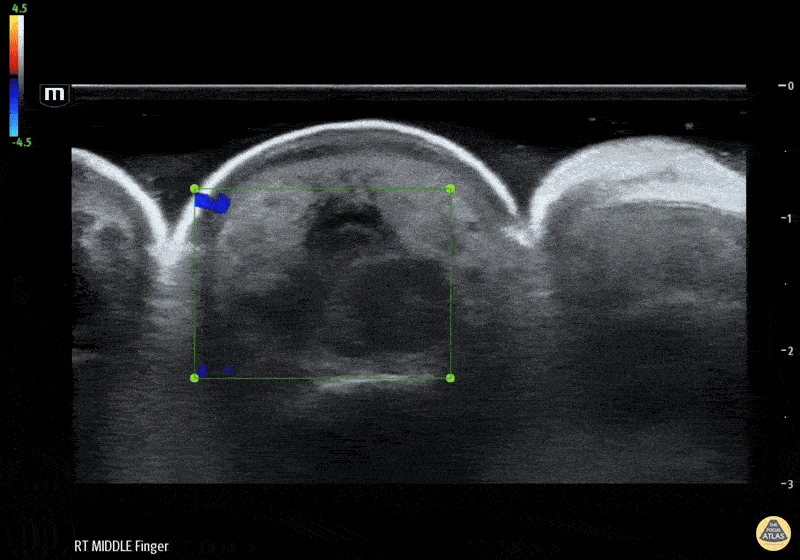

Musculoskeletal - Flexor Tenosynovitis Waterbath Ultrasound - Color Doppler

50 yo M presented to the ED after accidentally injuring his middle finger while welding, with reported fevers, finger swelling and all 4 Kanavel signs. Waterbath ultrasound shows fluid along the flexor tendon sheath extending distally. Hand consulted, patient taken to operative room for septic FTS. Erick Otiniano, MD MPH | DHREM PGY1 Fred Milgrim, MD | Director of Residency Ultrasound Education, Denver Health